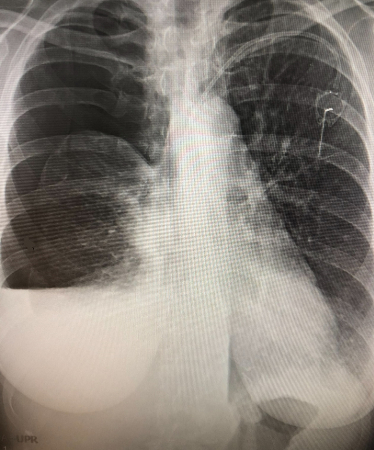

Entrapped lung with pneumothorax ex-vacuo. This patient had a malignant pleural effusion that had developed a thick visceral pleural cortical rind preventing re-expansion. Chest tube was for pleural effusion removal, not evacuation of air.

From the personal collection of Chris Kapp, MD; used with permission